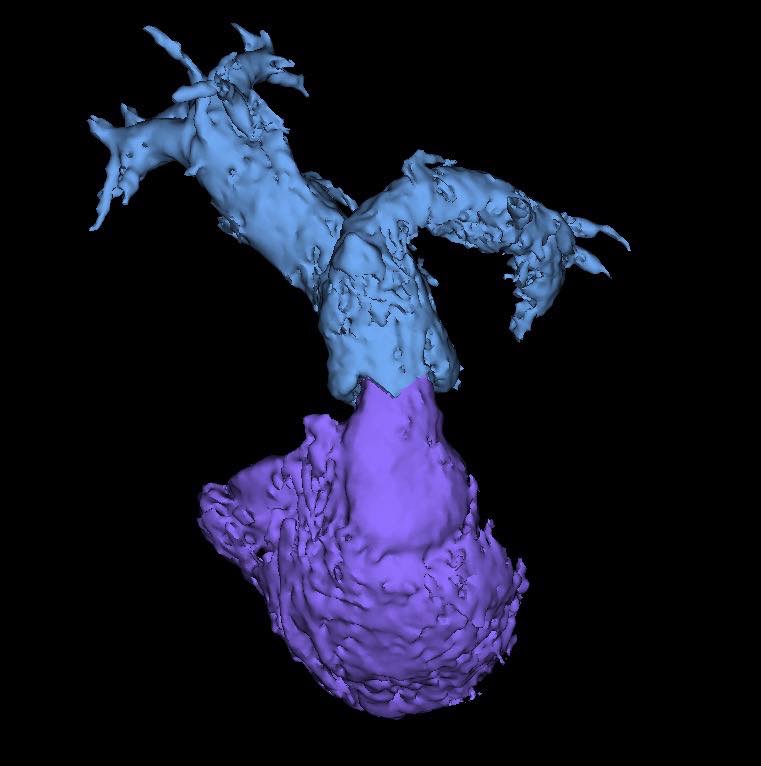

คณะแพทยศาสตร์ มช. สร้างความสำเร็จทางการแพทย์ ด้วยการรักษาโรคลิ้นหัวใจพัลโมนิกรั่ว (Pulmonary valve regurgitation) ผ่านสายสวน ในผู้ป่วยหญิงไทย อายุ 22 ปี ที่มีประวัติผ่าตัดรักษาภาวะ Tetralogy of Fallot มาก่อน และมีอาการของลิ้นพัลโมนิกรั่วรุนแรง

การใส่ลิ้นหัวใจพัลโมนิกเทียมผ่านสายสวนหัวใจ (Transcatheter pulmonary valve implantation; TPRI ) ในครั้งนี้ ทำผ่านทางหลอดเลือดดำใหญ่ บริเวณขาหนีบ จึงไม่ต้องผ่าตัดเปิดทรวงอก โดยกระบวนการรักษาและพักฟื้นผ่านไปได้ด้วยดี ไม่พบภาวะแทรกซ้อน ผู้ป่วยสามารถออกจากโรงพยาบาล 2 วันภายหลังการรักษา นับเป็นหนึ่งในความก้าวหน้าของนวัตกรรมการแพทย์เพื่อใช้รักษา ลดความเสี่ยงของภาวะแทรกซ้อนต่างๆ รวมถึงยกระดับคุณภาพชีวิตของผู้ป่วยได้

การแก้ไขลิ้นหัวใจพัลโมนิกรั่วมี 2 วิธี คือ การผ่าตัดเปิดทรวงอกเพื่อใส่ลิ้นหัวใจพัลโมนิกเทียม และ การใส่ลิ้นพัลโมนิกผ่านทางสายสวนหัวใจ การเปลี่ยนลิ้นทั้งสองวิธีนี้เมื่อเวลาผ่านไป 10-20 ปี ลิ้นพัลโมนิกเทียมจะมีโอกาสเสื่อมอีก ทำให้ผู้ป่วยประมาณ 1 ใน 3 จำเป็นต้องเปลี่ยนลิ้นหัวใจซ้ำอีกครั้ง ซึ่งในผู้ป่วยบางรายอาจจะต้องการการใส่ลิ้นพัลโมนิกเทียมไม่ว่าจะโดยการผ่าตัดหรือผ่านทางสายสวน 2-3 ครั้งในช่วงชีวิตหนึ่ง

การผ่าตัดเปิดทรวงอกในแต่ละครั้ง จะก่อให้เกิดพังผืด (fibrous adhesion) เพิ่มความยากลำบาก และความเสี่ยงในการผ่าตัดมากขึ้น การรักษาผ่านทางสายสวนจึงเป็นทางเลือกที่จะลดความเสี่ยงนี้ลง อีกทั้งยังสามารถใส่ลิ้นพัลโมนิกเทียมชิ้นใหม่ทับแทนชิ้นเก่าได้ (valve in valve procedure)